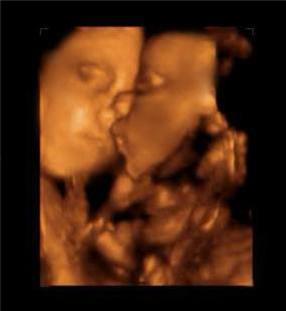

擁有雙胞胎寶寶父母當然都很幸福,雖然養育兒女付出了雙份的辛苦,但同時也收穫了雙份的歡樂。  他們在媽媽肚子的時候就已經頻頻互動,有時候還會親吻,打架!超級萌,超級感人!

雙胞胎居然在打架   其實雙胞胎是心有靈犀的,看下面的這兩對雙胞胎,你就知道有多羨慕了 1、當這對雙胞胎從媽媽肚子裡生出來的那一刻,竟讓醫院所有人都震驚了!!原來這對雙胞胎竟是.手拉手出生的! 而當寶寶生下來的一刻,大家都驚呆了  爸爸都感動的哭啦 2、雙胞胎中的弟弟出生就沒呼吸,哥哥給他加油打氣,居然拉起弟弟的手 出生時,弟弟被查出了胸部感染,需要靜脈注射抗生素,這時哥哥竟然把手伸過來緊緊握住了弟弟的手。 「不要怕,哥哥保護你。」  就在護士向媽媽解釋如何治療的時候,突然哥哥伸出手去摸瓊斯,弟弟感覺到了就伸手來回應,然後他倆的手緊緊的握在了一起。這一幕太令人難以置信了!